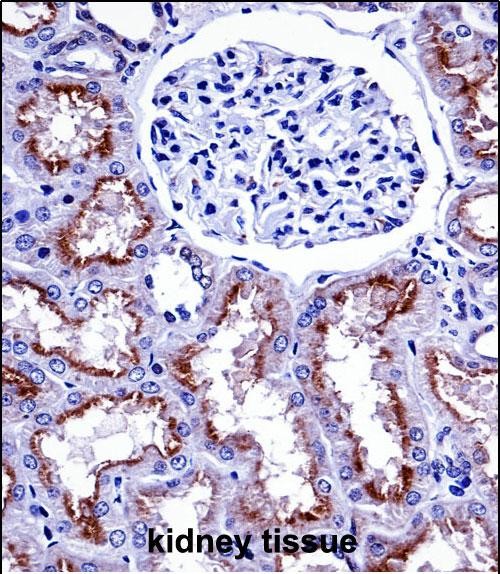

| IHC | 1/100-1/500 | Human,Mouse,Rat |

| Immunogen | This NOX4 antibody is generated from rabbits immunized with a KLH conjugated synthetic peptide between 124-153 amino acids from the N-terminal region of human NOX4. |

The NOX4 (N-term) antibody is a tool designed to detect the N-terminal region of NADPH oxidase 4 (NOX4), a key enzyme in reactive oxygen species (ROS) generation. NOX4. a member of the NADPH oxidase family, is constitutively active and primarily produces hydrogen peroxide (H₂O₂), influencing cellular signaling, differentiation, and stress responses. Unlike other NOX isoforms, NOX4 is unique in its dependence on regulatory subunits (e.g., p22phox) and its localization to intracellular membranes, including mitochondria and endoplasmic reticulum. The N-terminal domain of NOX4 plays a role in protein-protein interactions and subcellular targeting, making it critical for enzymatic activity and functional specificity.

The NOX4 (N-term) antibody is commonly used in techniques like Western blotting, immunohistochemistry, and immunofluorescence to study NOX4 expression, localization, and regulation in tissues or cells. Its specificity for the N-terminus helps distinguish NOX4 from other NOX isoforms, minimizing cross-reactivity. Researchers employ this antibody to explore NOX4's involvement in pathological processes such as fibrosis, inflammation, cancer progression, and cardiovascular diseases, where dysregulated ROS production contributes to tissue damage or signaling abnormalities. Validation of the antibody typically includes knockout controls or peptide blocking assays to confirm target specificity. Understanding NOX4's role via this antibody has advanced insights into redox biology and potential therapeutic targeting of ROS-related disorders.